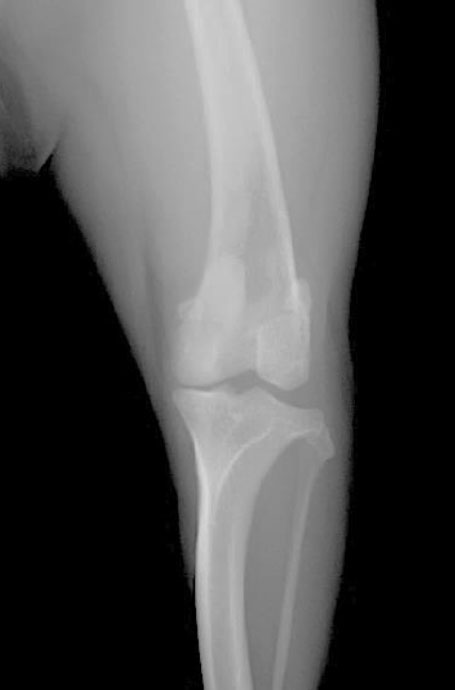

術後

レントゲンチェック